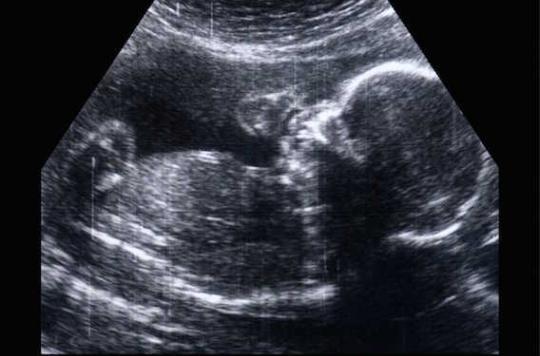

Deux risques ont en effet été identifiés. Le premier, relaté dans la littérature scientifique dans les années 1980, est d’ordre tératogène : le fœtus exposé à la Dépakine dans le ventre de sa mère a un sur-risque de 10 % de naître avec une malformation grave (spina bifida, notamment). Par ailleurs, les enfants exposés in utero à cette molécule présentent un sur-risque de 30 à 40 % de développer des troubles neurocomportementaux.